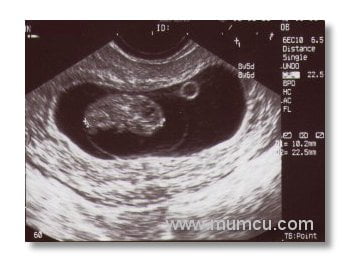

6 haftalık ikiz gebelik

Vajinal ultrasonografi